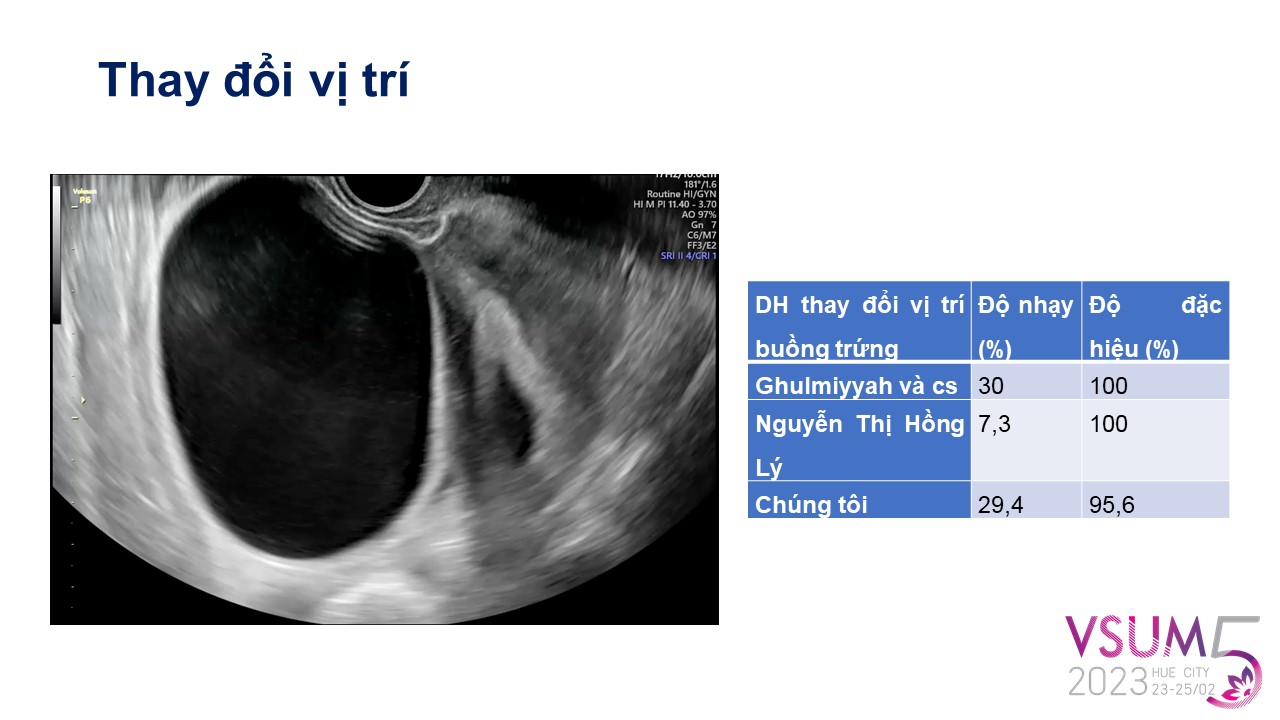

Giá trị của siêu âm ngả âm đạo trong đánh giá xoắn phần phụ